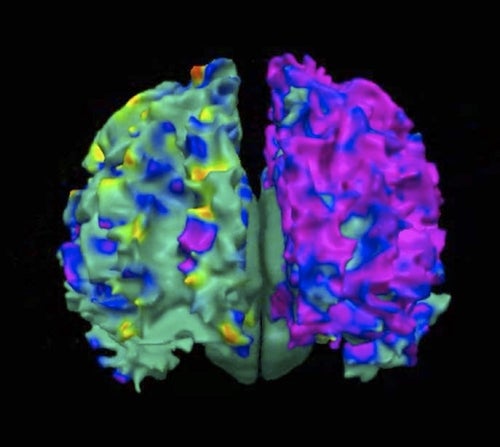

- The purple area in this image of a newborn’s brain shows damage in the part of the brain that helps with language, math and logic. (Courtesy of Children’s Hospital of Los Angeles Saban Research Institute)

Look at this image of a newborn’s pollution-damaged brain, from the Saban study. A healthy brain should be all green. The purple area in this image shows damage in the part of the brain that helps with language, math, and logic.